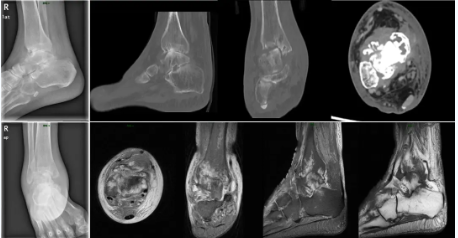

术前患者踝关节影像

入院后经完善相关检查和详细分析病情后,诊断为右踝关节终末期骨性关节炎合并痛风性关节炎。以往终末期踝关节炎患者大多采用踝关节融合术,虽能解决患者关节疼痛的问题,但术后踝关节活动功能丢失,步态发生显著改变,下蹲、爬坡等日常生活也会受到诸多限制,容易造成周围关节的继发性损伤,带来新的疼痛和周围相邻关节的退变加速,这对于要求保留踝关节活动功能且年龄只有56岁的高先生来说难以接受。

钟环主任医师团队综合分析,患者想既要解决疼痛问题又能较好地保留踝关节的活动度,实施右侧全踝关节置术是最佳的选择。根据既往我院开展的踝关节置换手术经验,高先生的骨骼条件并无严重畸形,整个手术过程可以通过3D打印术前规划和辅助截骨获得更加精准的植入效果。最终,关节外科团队与患者及家属充分沟通,决定应用3D打印技术为高先生实施标准化假体的右侧全踝关节置换术。随后,钟环主任与手术团队成员在计算机3D模型前进行反复模拟演练,充分考虑标准化踝关节置换手术技术实施过程中的关键节点和术中潜在风险,准备了多套预案以应对术中情况的变化。